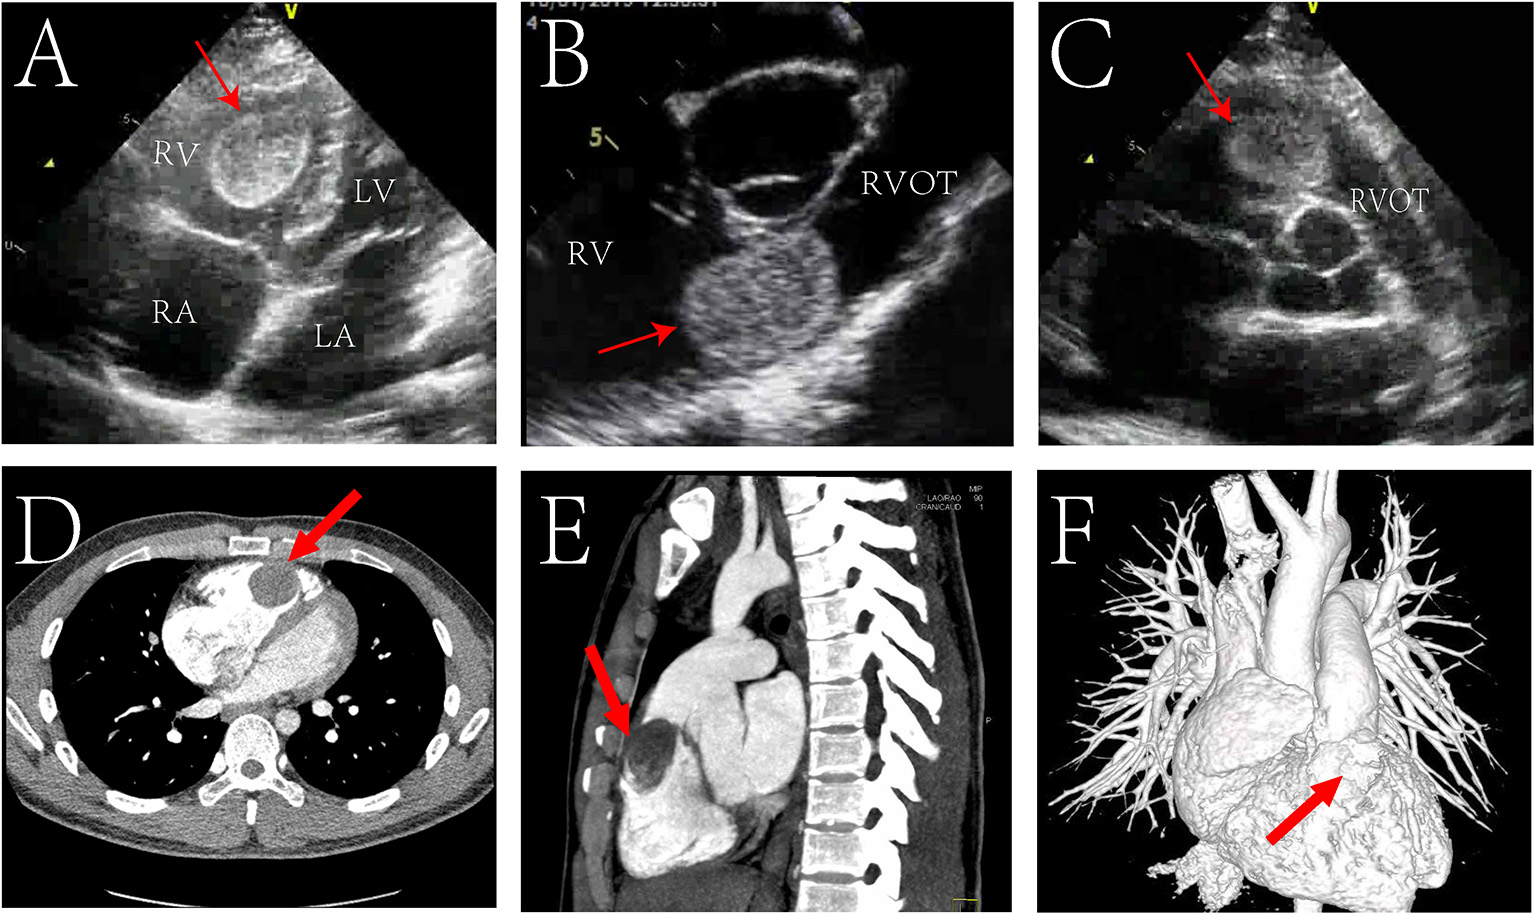

Electrocardiogram suggested sinus rhythm with sharpened T waves. No notable abnormalities were found following chest X-ray examination. Echocardiography showed enlargement of the right atrium (50 mm), right ventricle (46 mm), and right ventricular outflow tract (31 mm) in diameter. Left atrium, left ventricle, and aorta were normal in diameter with a left ventricular ejection fraction of 74%. However, a hyperechoic space occupying mass with clear boundary (approximately 36 × 30 mm in size) was found in the right ventricle near the outflow tract (Figures 1A–C). The mass was connected to the anterior wall of the right ventricle by a pedicle and oscillated with the cardiac cycle. The tricuspid valve opened well but could not close properly, and Color Doppler Flow Imaging (CDFI) showed regurgitation under the tricuspid valve. Affected by the mass, the blood flow in the right ventricular outflow tract accelerated to 3.8 m/s, and the pressure difference (PG) across the pulmonary valve increased to 58 mmHg. Computed tomography angiography (CTA) also showed that the right atrium and right ventricle were enlarged, and a round filling defect of about 3.5*4.2*2.2 cm was seen in the right ventricular outflow tract (Figures 1D–F). Its density was roughly equivalent to that of the myocardium with clear boundaries.

FIGURE 1

www.frontiersin.org

Figure 1. Echocardiogram pre-operatively showing a mass (red arrow) located in the in the right ventricular outflow tract (RVOT) in transthoracic four chamber cross section (A), transthoracic short axis section of aorta (B), transesophageal short axis section of aorta (C). Preoperative cardiac Computed Tomography (CT) showed a mass (red arrow) in the RVOT in transverse view (D), sagittal view (E); CT angiography (CTA) showed a filling defect (red arrow) in the right ventricular outflow tract (F). RV, right ventricle; LV, left ventricle; RA, right atrium; LA, left atrium.